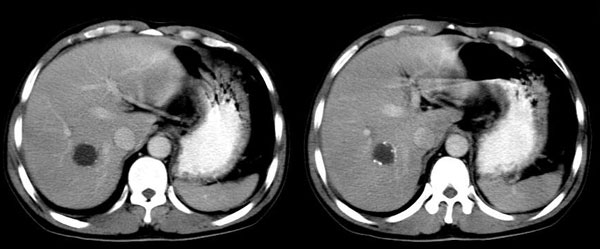

男,44岁,解黒便18天,胃镜:胃小角溃疡性质待查,表浅性胃炎。b超肝右叶占位。ct平扫肝右叶见一囊性占位,ct值:18hu,壁呈带状高密度钙化,增强扫描未见强化。考虑:囊肿?但壁钙化第一次见,不能确定,病人是南方石山地区,未到过牧区,能否排除包虫?

增强扫描:病灶未强化。

延时4分钟

右肝后叶内圆形囊状影,包膜完整,断续钙化.

意见:右肝囊肿并钙化